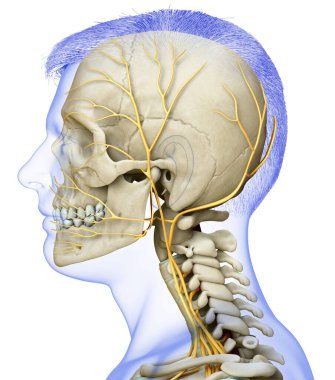

iskelet adam yan görünüm baş ve sinir sistemi

Özel Boyut

(5000 x 5000, jpg)